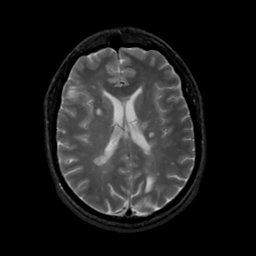

MR Study #8, March 31, 1991 -- Slice #30